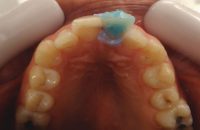

5- Segunda sesion de blanqueo interno 5 – Segunda sesion de blanqueo interno Deja un comentarioLo siento, tenés que estar conectado para publicar un comentario.